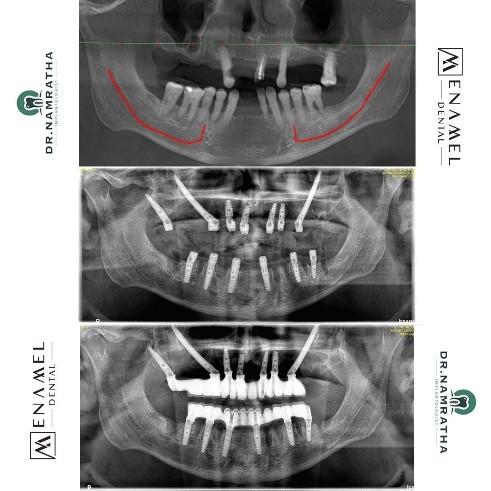

Upon his visit to Enamel Dental Clinic, Dr. Namratha Chandrahari conducted a thorough examination, including advanced diagnostic imaging. A Cone Beam Computed Tomography (CBCT) scan was used to evaluate the underlying bone structure and to plan the placement of implants with precision. The scan confirmed severe bone loss, which required a more advanced solution.

Given the extent of Jason’s dental concerns and the lack of sufficient bone for traditional implants, Dr. Namratha recommended a customized solution involving All-on-6 conventional implants in combination with zygomatic implants on both sides. This innovative approach would not only address bone loss but also provide a permanent, functional, and aesthetically pleasing solution for his smile.

Dr. Namratha meticulously planned and executed the All-on-6 implants combined with zygomatic implants, ensuring optimal placement for maximum stability. The All-on-6 technique involves placing six implants in the upper or lower jaw to support a full arch of fixed teeth, while zygomatic implants are specially designed to anchor the prosthesis in patients with significant bone loss.